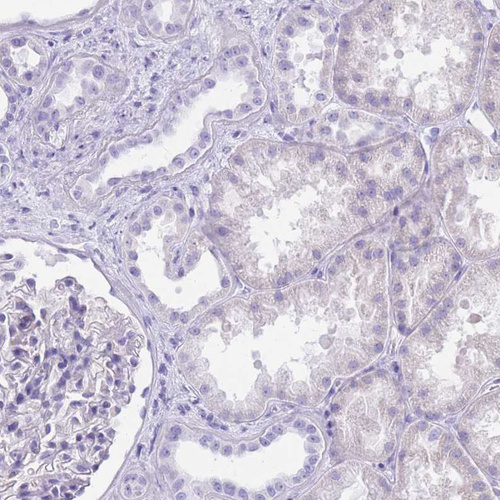

Immunohistochemistry analysis in human adrenal gland and kidney tissues using HPA048979 antibody. Corresponding CYP21A2 RNA-seq data are presented for the same tissues.